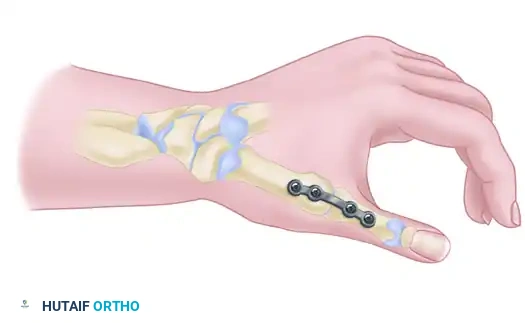

- Fracture Management: Arthroscopically assisted reduction and internal fixation (ARIF) of intra-articular distal radius fractures, scaphoid fractures, and perilunate fracture-dislocations. It ensures anatomic restoration of the articular step-off and allows concurrent management of associated soft-tissue injuries.

- Bone Excision Procedures: Radial styloidectomy, partial distal ulnar resection (wafer procedure), proximal row carpectomy, and excision of the proximal pole of the scaphoid.